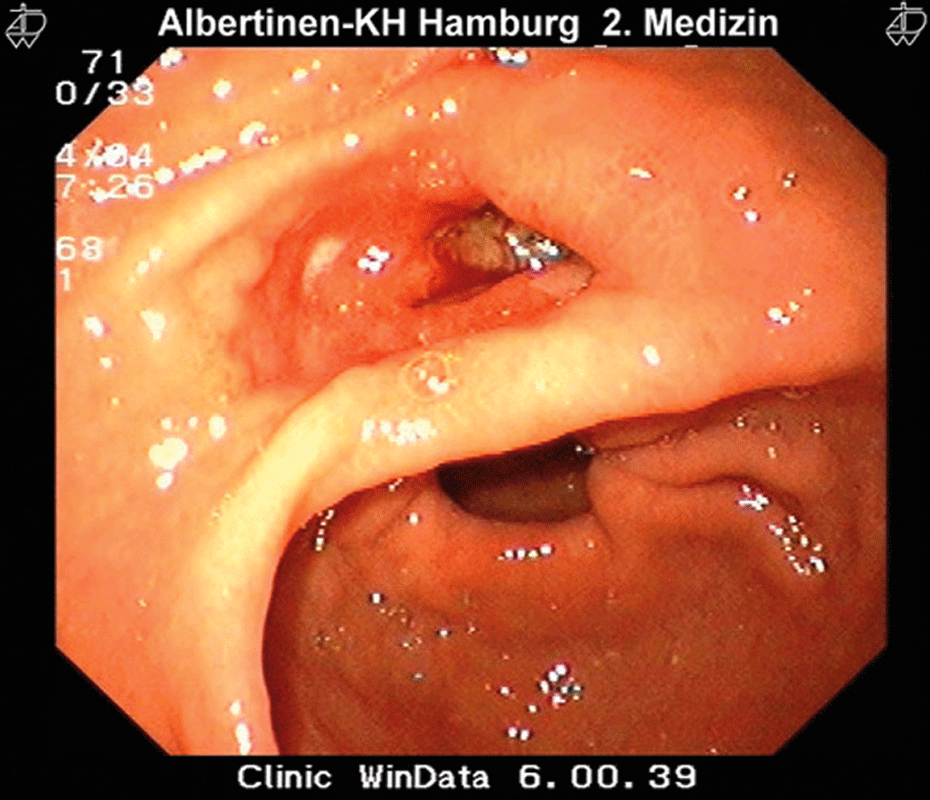

Hier hat sich das Geschwür schon bis in den Zwölffingerdarm durchgearbeitet. Hier hat sich das Geschwür schon bis in den Zwölffingerdarm durchgearbeitet. © Albertinen-Krankenhaus Hamburg/ endoskopiebilder.de